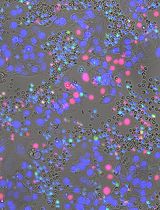

The figure shown below shows the representative images obtained from the MDA. The black arrows indicate the sprouting angiogenic HRMEC tube–like structures, which have invaded the secondary Matrigel layer from the primary layer (Figure 8).

Figure 8. Representative photographs obtained from the Matrigel Duplex Assay (MDA). The black arrows indicate the angiogenic tube–like structures invading into the secondary layer.